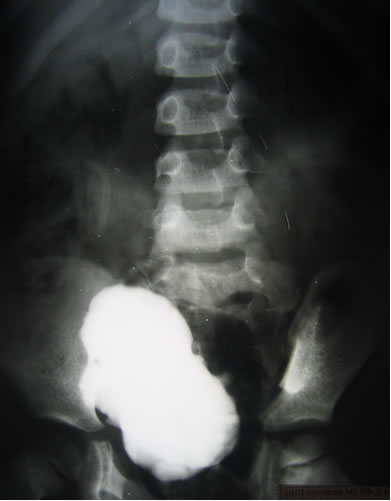

Цистография